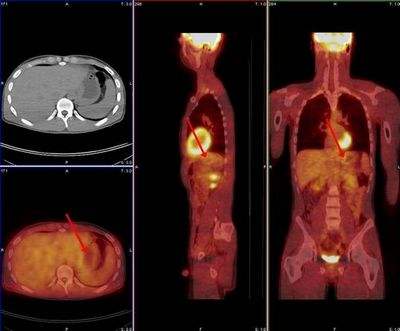

前列腺癌患者的印戒细胞癌多发骨···